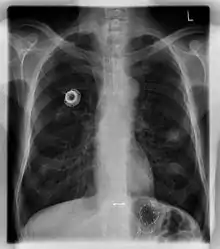

The port is usually inserted in the upper chest (known as a "chest port"), just below the clavicle or collar bone, with the catheter inserted into the jugular vein.

A port consists of a reservoir compartment (the portal) that has a silicone bubble for needle insertion (the septum), with an attached plastic tube (the catheter). The device is surgically inserted under the skin in the upper chest or in the arm and appears as a bump under the skin. It requires no special maintenance other than occasional flushing to keep clear. It is completely internal so swimming and bathing are not a problem. The catheter runs from the portal and is surgically inserted into a vein (usually the jugular vein or less optimally the subclavian vein). Ideally, the catheter terminates in the superior vena cava or the right atrium. This position allows infused agents to be spread throughout the body quickly and efficiently.

The port is then sutured on two sites to the underlying muscles. The tip of the catheter is checked for kinks and position using a fluoroscope. Besides that, aspiration of blood and contrast injection through the chemoport can also be used to confirm the position. The port is the closed in two layers (subcutaneous tissue is sutured first, followed by the skin). Sterile dressing is then placed on the port.[3] The optimum site to park the tip of the catheter is at the cavo-atrial junction or with margin of error of not more than 4 cm above the junction.[3]

A follow-up on a chest radiograph can immediately detect complications associated with the procedure such as pneumothorax, hemothorax and malpositions of the catheter. However, routine chest radiography is not needed due to the low complication rates associated with the procedure. The chest radiograph is only done if there is clinical suspicion of a complication.[4]

Ports can be put in the upper chest or arm. The exact positioning itself is variable as it can be inserted to avoid visibility when wearing low cut shirts, and to avoid excess contact due to a backpack or bra strap. The most common placement is on the upper right portion of the chest, with the catheter itself looping through the right jugular vein, and down towards the patient's heart.